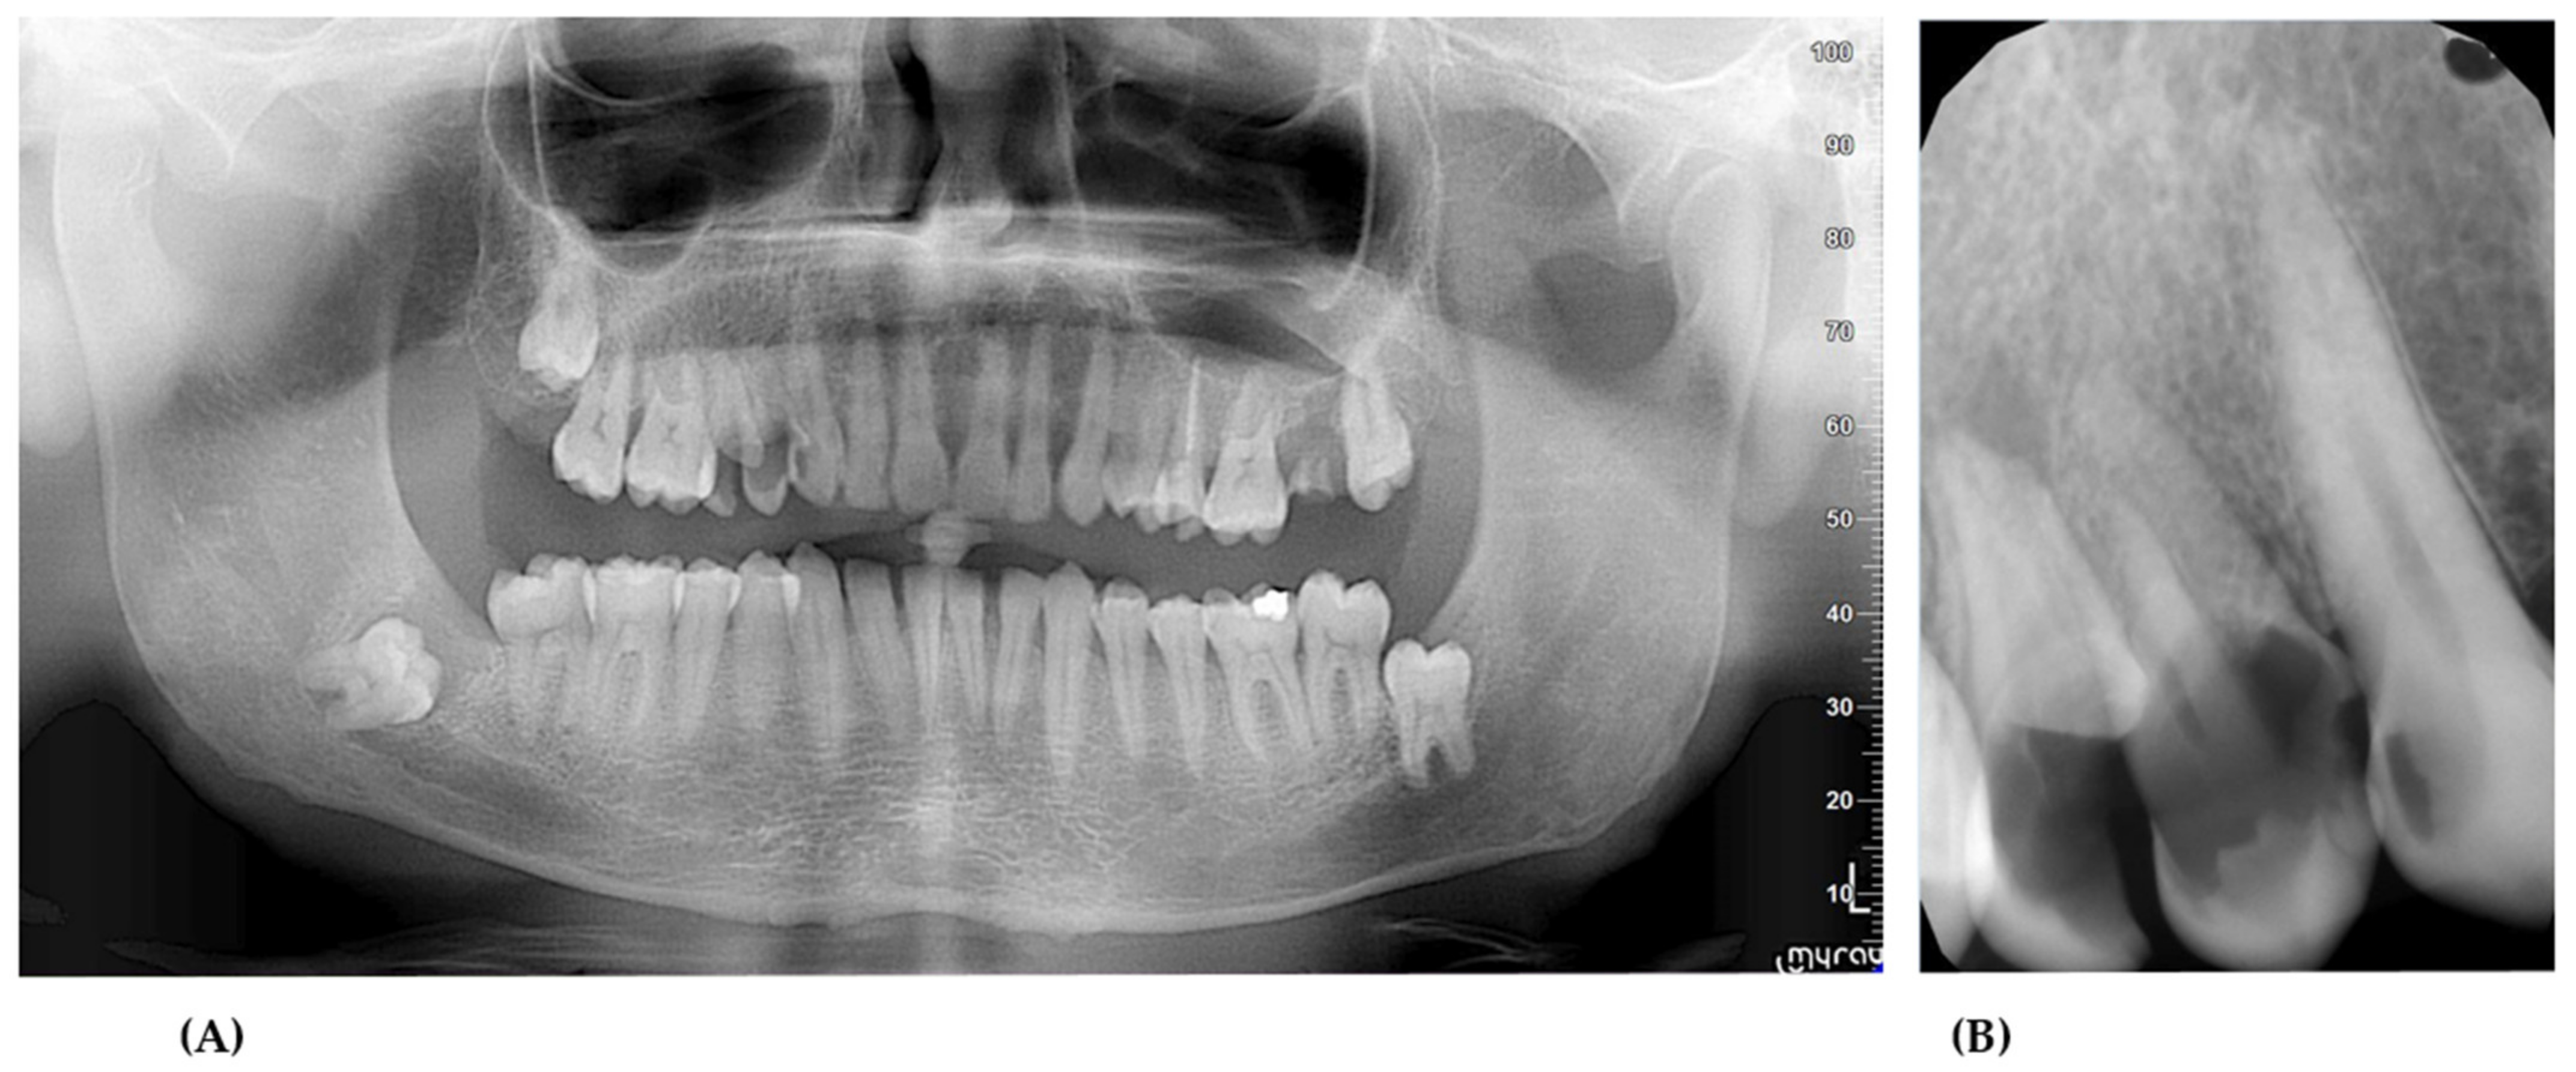

2. Case Presentation